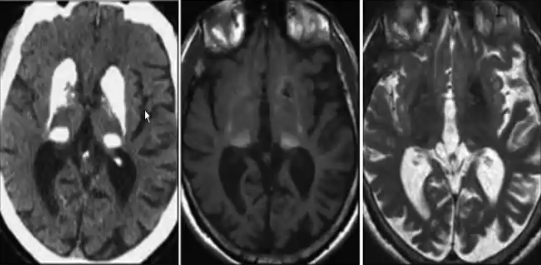

表现为广泛的深部灰质核团的对称性钙化,主要为苍白球,其余病变部位包括:壳核、尾状核、丘脑、小脑齿状核。